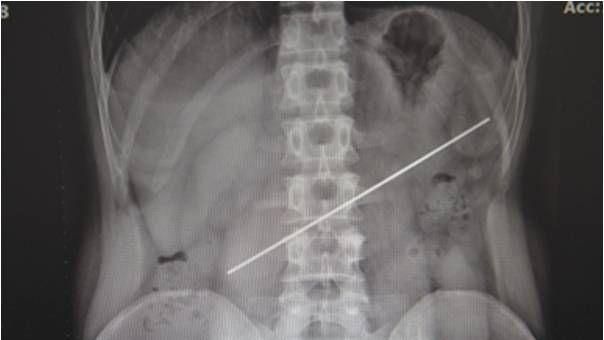

據陸媒報導,男子23日在家人的陪伴下看診,乍看之下並無異狀,直到醫生幫他照X光後

,才發現他的胃裡有一根20公分的鋼條,畫面相當嚇人,其中一端甚至已經將胃壁戳破。

▲男子胃部有一根20公分鋼條。